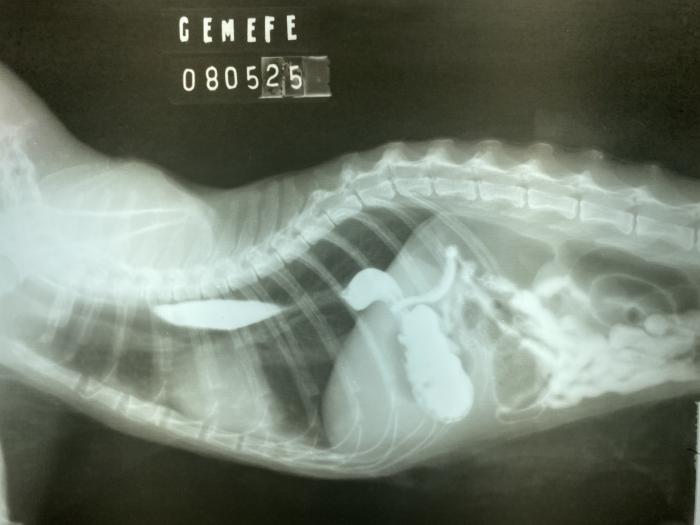

- Radiografías contrastadas con iopamidol (Iopamiron ®300). El paciente presenta una sonda nasoesofágica, por donde fue colocado el contraste (Figura 4A-B).

Figura 4. (A) Primera imagen constrastada, con sonda colocada hasta décimo espacio intercostal. (B) Segunda imagen contrastada, se retiró la sonda hasta el tercer espacio intercostal.